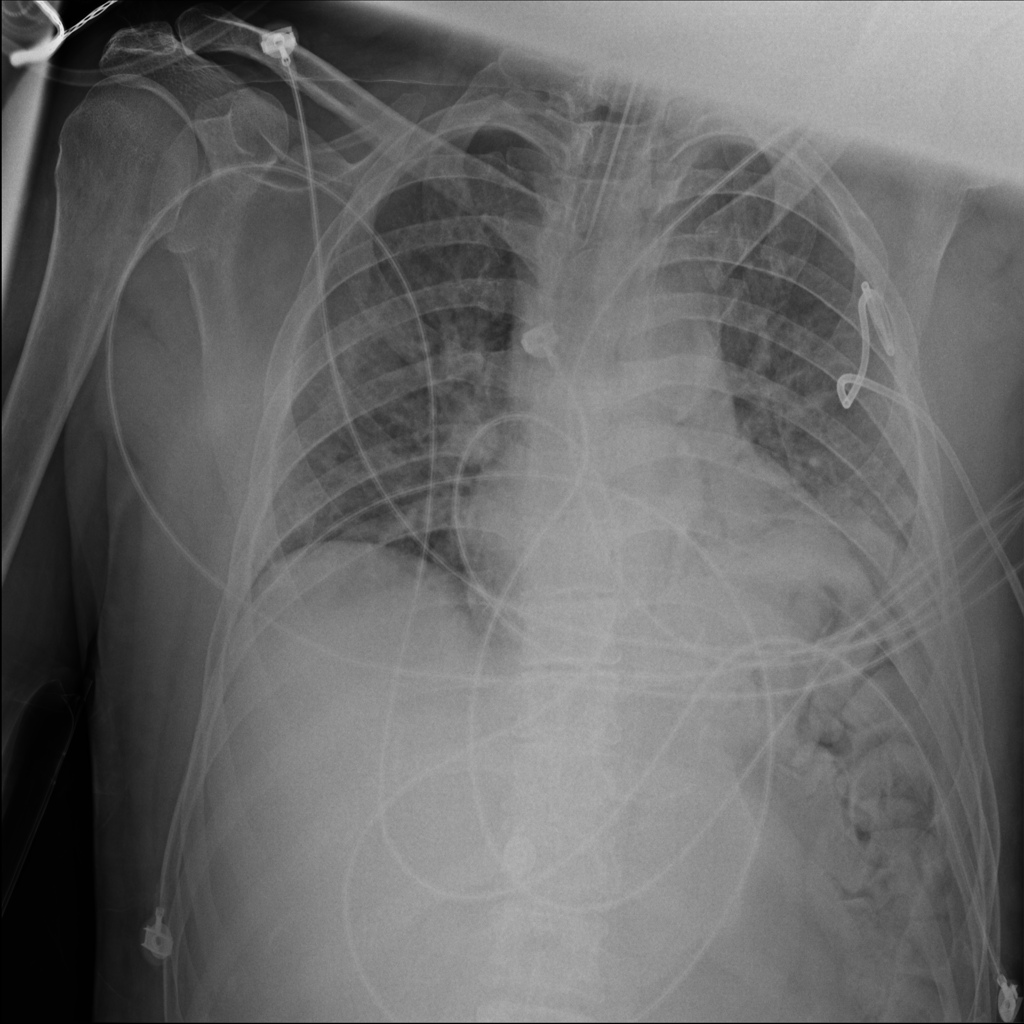

PAT-3384 · IMG-054Atelectasis

PAT-3384 · IMG-054

AP